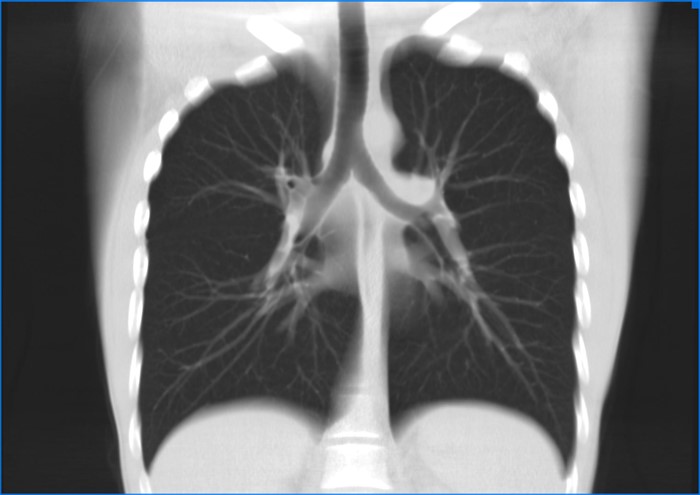

Компьютерная томография легких – это современный, информативный, неинвазивный метод обследования легких, бронхов, сердца, крупных сосудов грудной полости, который позволяет с высокой степенью вероятности выявить патологические изменения в органах и тканях на самых ранних этапах развития заболевания.

Метод позволяет получить ряд изображений послойного строения органов грудной полости. Толщина таких слоем может составлять порядка 1 мм. Это позволяет выявить даже не большие по объему образования.

Более информативными метода исследования состояния органов и тканей грудной полости являются спиральная и мультиспиральная компьютерная томография. На томографах этих двух типов можно получать более качественные и детальные двух — и трехмерные изображения отдельных органов и анатомических образований, а доза облучения, которую получает за одно обследование пациент, существенно ниже.

Компьютерная томография (КТ) легких — это метод медицинской визуализации, который использует рентгеновские лучи для создания детализированных изображений легких и окружающих тканей. Процедура обычно занимает всего несколько минут и включает в себя лежание на специальном столе, который перемещается через кольцевой сканер. В некоторых случаях может использоваться контрастное вещество для улучшения визуализации.